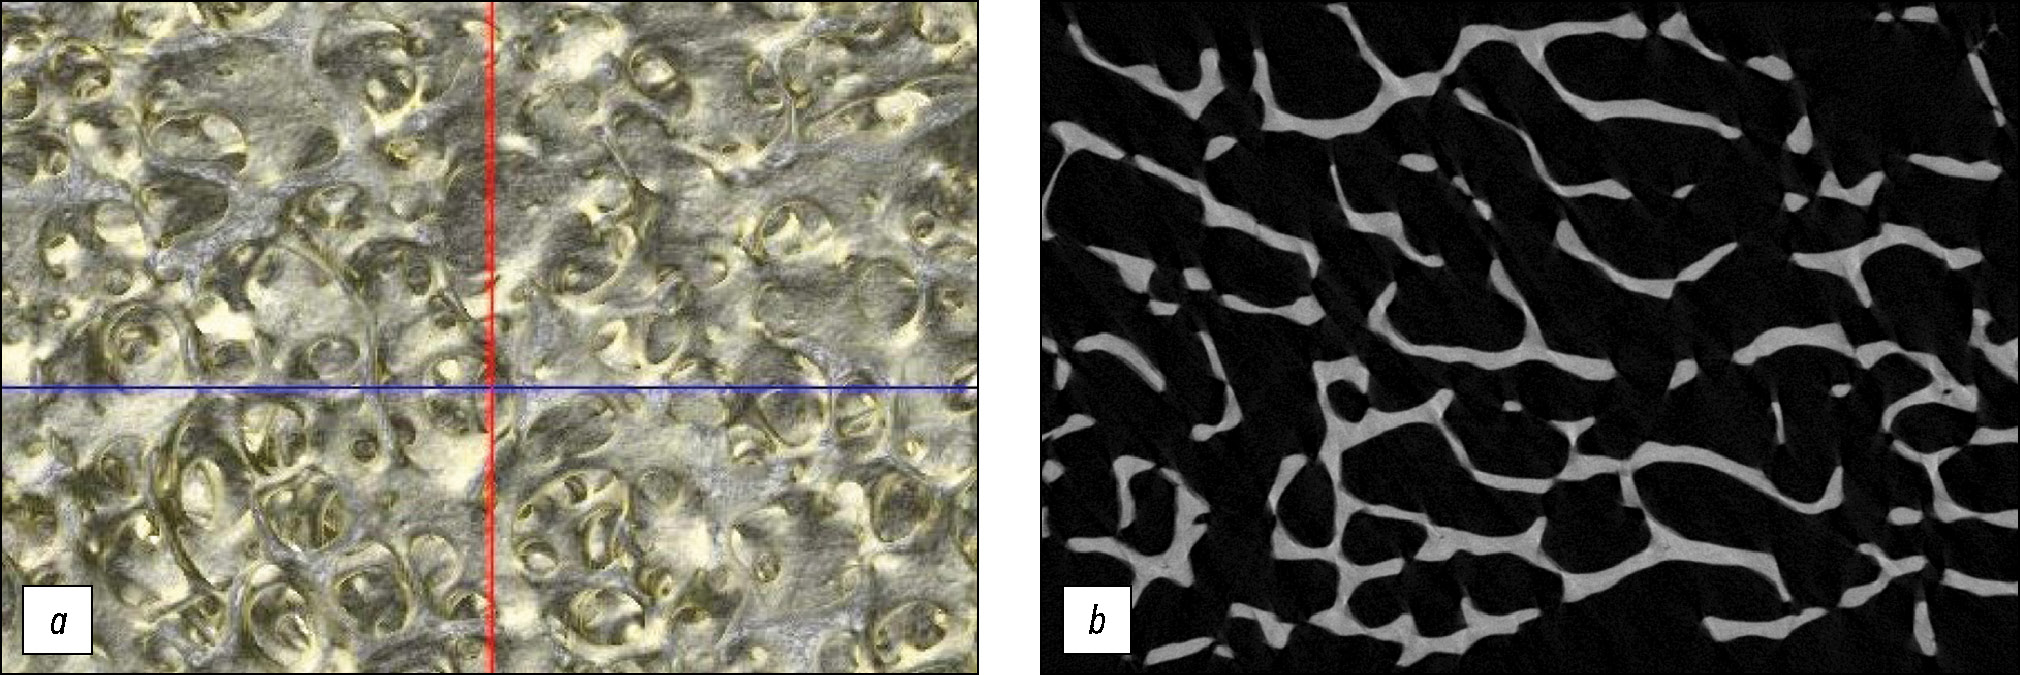

Рис. 2. Результаты томографического исследования образца, очищенного по методике 4-3: a — 3D-реконструкция, b — микро-КТ срез.

Fig. 2. Tomographic results of the sample purified by technique 4-3: a — 3D reconstruction, b — micro-CT slice.

Эффективность использования всех этих методов подтверждается результатами томографического и гистологического исследований: сохранностью микроархитектоники (костные трабекулы формируют характерную для нормальной губчатой кости ячеистую сеть, костный матрикс имеет нормальную тонковолокнистую структуру), лизисом клеток (в лакунах сохранено меньше 10% остеоцитов с ядрами, остальные лакуны пустые) и полным удалением клеточных остатков (мембраны адипоцитов костного мозга отсутствуют). На рис. 2, 3 приведены результаты томографического и гистологического исследований для образца, очищенного по методике 4-3. Результаты исследований образцов, очищенных по методикам 4-1 и 4-2, представляют собой аналогичную картину.